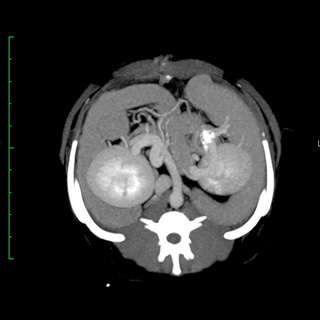

CT画像診断

CT検査により、通常の画像検査では検出しにくい病気の早期発見・診断につながる可能性が高まります。

CT画像の検査・読影のみも受け付けております。当院では画像診断アドバイザーとして柿崎竹彦先生(北里大学獣医学部獣医学科 獣医放射線学研究室講師)からアドバイスをいただいております。